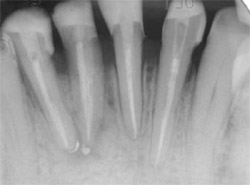

Root canal treatments using the crown-down technique and GuttaFlow filling material were performed on the canals of each case (Figure 5 and Figure 6). The crown structure of the teeth in Case One was restored with ParaPost Fiber White, and in Case Two with ParaPost Fiber Lux after post removal (Figure 7 and Figure 8). The posts were cemented with ParaCem, and the build-ups with ParaPost ParaCore, and full metal-ceramic crowns were posteriorly cemented as a part of the patients’ general treatment plan (Figure 9, Figure 10, Figure 11). Both cases were followed up on clinically for 12 months.

On the final periapical radiograph following obturation, the apical space, width, and length of the root canals were checked (Figure 5 and Figure 8). The working field was isolated with a rubber dam. Two thirds of the total canal length of the canals was used for the post space. The GuttaFlow was removed to the desired depth using a Touch’n Heat 5004 instrument (SybronEndo, Orange, CA) leaving 5 mm of GuttaFlow in the canals (Figure 8 and Figure 12).

A rotary reamer was selected according to the canal thickness on the radiograph using a template provided in the post system in both cases. The canals were prepared using a low-speed handpiece. For Case 1, a 4.5-mm rotary reamer was selected for the canals. ParaPost Fiber White drills was used with a slow-speed contra-angle. The 4.5 ParaPosts Fiber White were cut at the apical aspect to the required length with a diamond-finishing bur (Figure 7) in Case 1. A 5.5 ParaPost Fiber Lux was used in Case 2 (Figure 8).

| Figure 5 Root canal treatment of teeth Nos. 23 through 26 using GuttaFlow. | Figure 6 Root canal treatment of tooth No. 8 using GuttaFlow with gutta-percha master cone. | ||||||||

| Figure 7 ParaPost Fiber White posts adapted and ready for cementation. | |||||||||